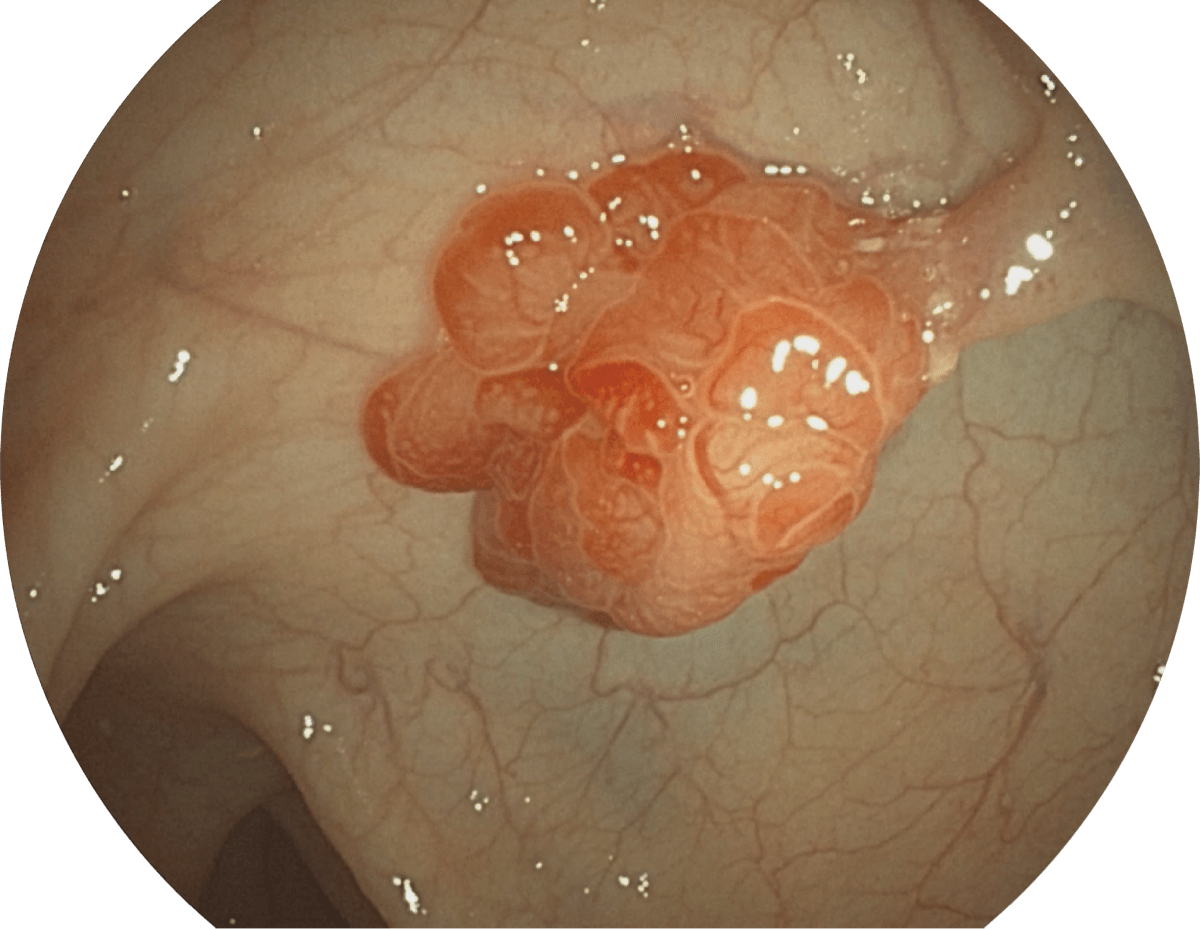

• 聚谱成像技术

(Spectral Focused lmaging, SFI)

图像具有高亮度、高黏膜血管颜色对比度的特点,且不改变粘液、食物残渣、粪便的基本颜色,可在中远景下进行观察,助力消化道早期疾病的诊断。

• WL

• SFI

• VIST